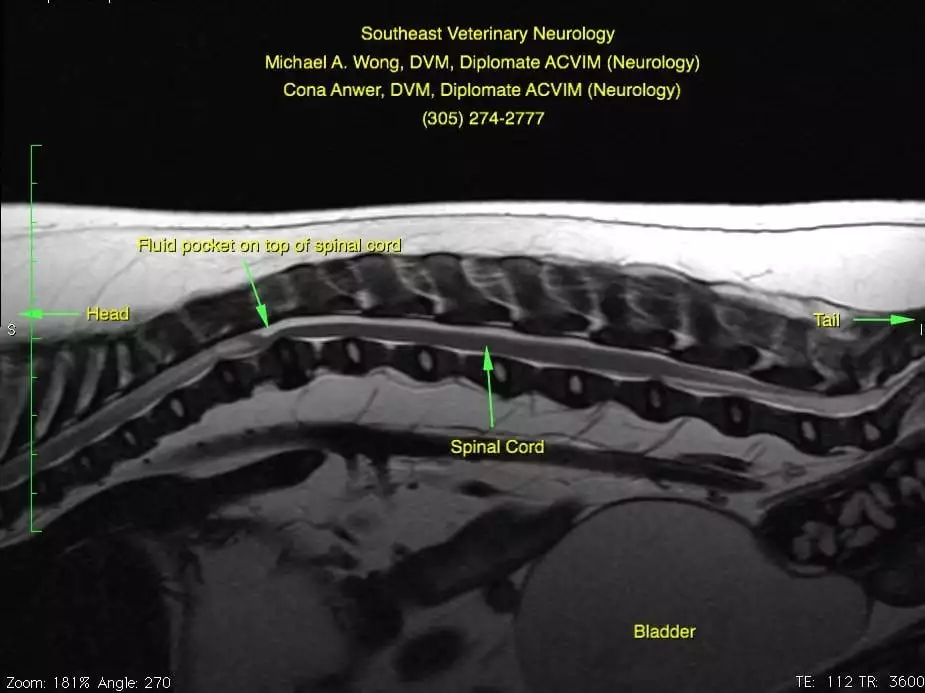

Magnetic resonance imaging (MRI) of Wellington’s thoracolumbar spine was performed.

Wellington has a fluid buildup dorsal to the spinal cord that is compressing the spinal cord ventrally. Additionally, cranial to the dorsal buildup of cerebrospinal fluid (CSF), you can see that there is increased signal (“brightness”) within the spinal cord. This is the ‘classic’ finding of a relatively newly recognized disease. There are several different names that neurologists have used for this disease including “Pug Myelopathy”, “Pug Constrictive Myelopathy”, “facet hypoplasia”, “subarachnoid diverticulum” and others. Although little is published about this condition, in my experience, it is the most common cause of mid-back spinal cord problems in Pugs.